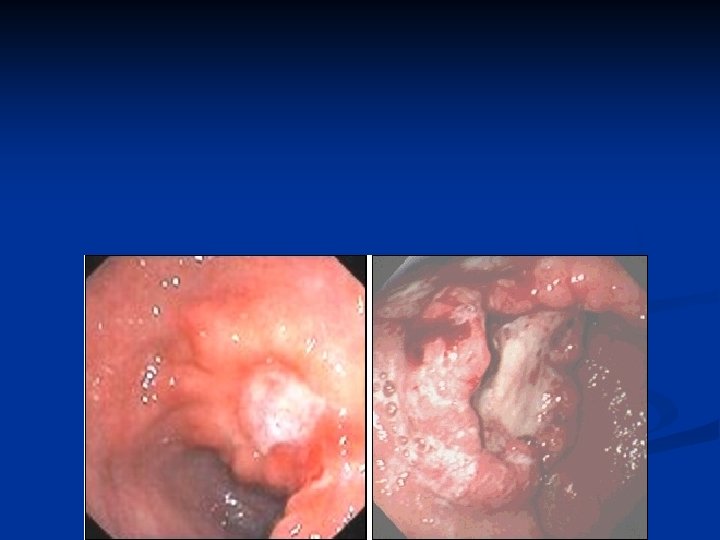

n Macroscopic – Borrmann n n Type I - polipoid well defined Type II – polipoid with marked infiltration Type III – ulceratio with infiltrated margins Tip IV – linitis plastica Microscopic – OMS n n n n n Adenocarcinoma – intestinal, difuse Adenocarcinoma papilary Adenocarcinoma tubular Adenoacrcinom mucinos (>50% mucinous cells) Signet cells carcinoma (>50% signet cells) Adenosquamos carcinoma Squamos cell carcinoma Small cells carcinoma Nondiferentiated altele